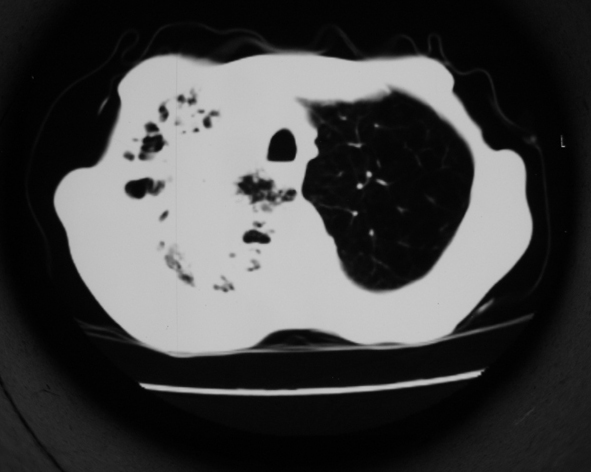

男53岁,咳嗽气短,以往身体健康.

右肺上叶多发多形态空洞及增殖灶,可见团块钙化,胸膜肥厚、粘连,考虑继发型肺结核可能性大

1.右肺上叶干酪性肺炎,2。肺气肿,肺大泡

右肺上中叶结核干酪性肺炎

右肺中上叶干酪性肺炎。

1.右肺上叶干酪性肺炎,2。肺气肿,肺大泡。支持!

支持右上肺继发性肺结核并干酪性肺炎,右肺大泡,左肺代偿性气肿。